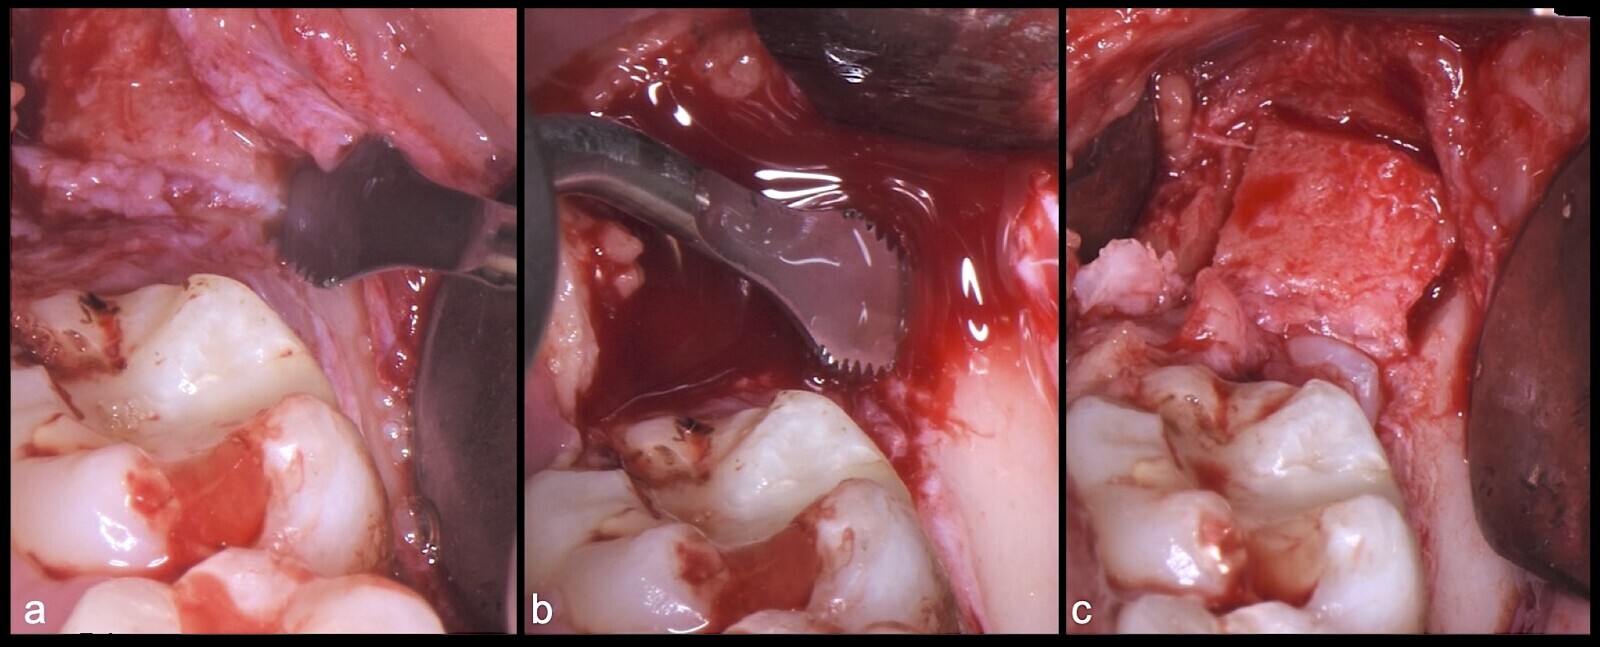

Figura 15. Vista clínica de la pieza 3.8 retenida (a). Incisión intrasulcular vestibular y distal e incisión vertical por mesial de 3.7 (b). Incisión horizontal en dirección distal de la pieza 3.7 con punta de corte del electro bisturí (c).

Figura 16. Cauterización con inserto de punta de coagulación del electro bisturí (a). Elevación del colgajo (b). Osteotomía con el inserto plano de corte de punta aserrada del piezoeléctrico (c).

Figura 17. Osteotomía con el inserto plano de corte de punta aserrada del piezoeléctrico (a, b). Demarcarción de los límites de la ostectomía del fragmento óseo (c).

Figura 18. Finalización de la osteotomía del primer fragmento óseo con inserto plano de corte de punta aserrada del piezoeléctrico (a, b, c).

Figura 19. Retiro del primer fragmento óseo (a, b). Extirpación del segundo bloque óseo con el inserto plano de corte de punta aserrada (c).

Figura 20. Retirada del segundo fragmento óseo (a). Ampliación de la ventana ósea con el inserto plano de corte de punta aserrada (b).